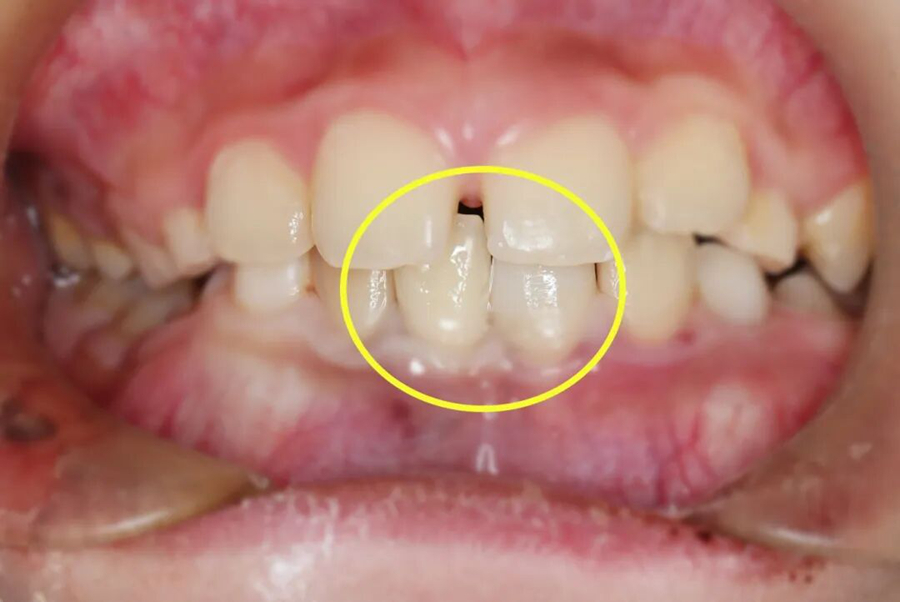

第二步,冠折露髓牙齿修复

针对冠折露髓的牙齿,救治团队在无痛辅助和显微镜下,彻底清除根管内的感染组织,进行严密的三维根管填充,建立无菌的内部环境。紧接着采用仿生树脂材料,通过分层分色堆塑技术,精准复原牙齿的天然形态和色泽,既解决了感染隐患,又恢复了牙齿的美观和咬合功能。

牙齿失而复得,小千一家人悬着的心终于落地了,对杨主任团队的精湛医术连连致谢。